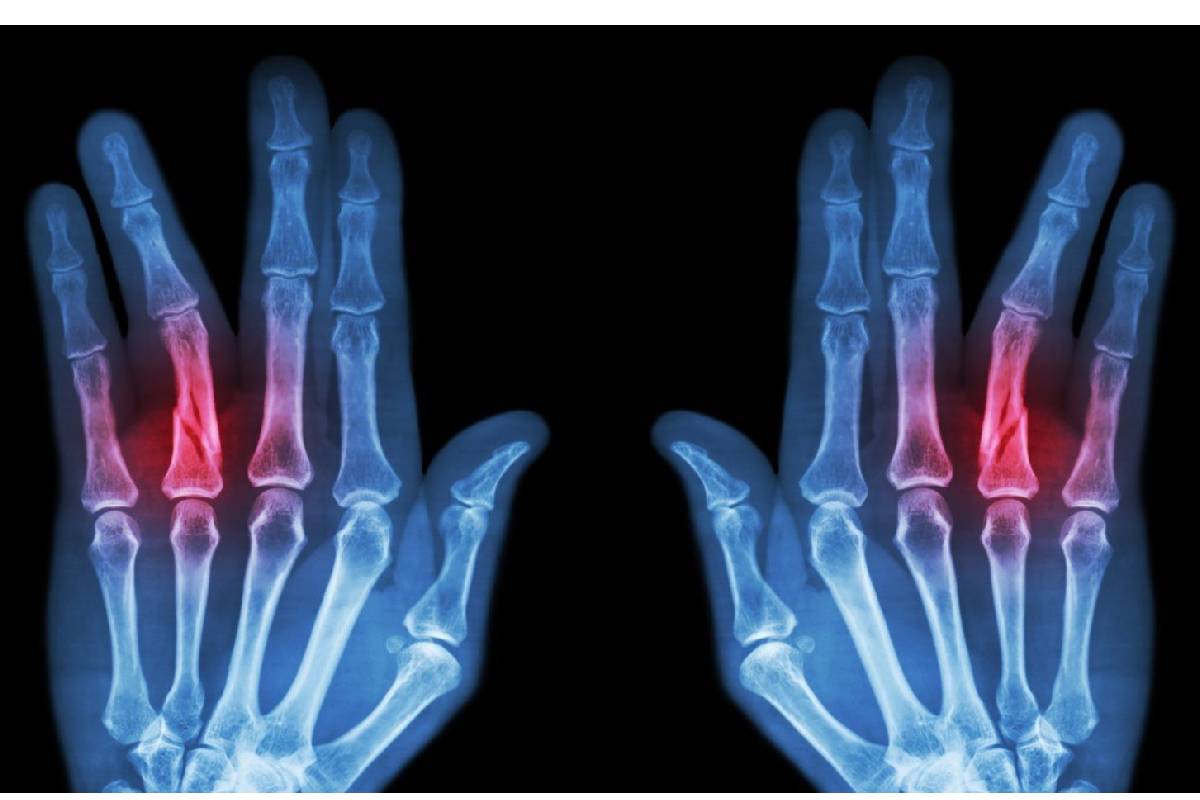

اگر به شکستگی انگشت خود شک دارید، حتماً به پزشک متخصص ارتوپد مراجعه کنید. تشخیص در خانه ممکن نیست. پزشک ابتدا انگشت شما را معاینه فیزیکی میکند و در مورد چگونگی آسیب از شما سوال میپرسد. برای تأیید نهایی تشخیص، از تصویربرداری با اشعه ایکس (رادیوگرافی) استفاده میشود. عکس رادیوگرافی محل دقیق شکستگی، نوع آن و میزان جابجایی استخوان را به وضوح نشان میدهد.

انواع شکستگی انگشت دست

شکستگیها بر اساس شدت و شکل آسیب به دستههای مختلفی تقسیم میشوند:

- شکستگی بسته: در این نوع، استخوان شکسته اما پوست روی آن سالم است.

- شکستگی باز: این نوع شکستگی شدیدتر است و در آن، استخوان شکسته پوست را پاره کرده و بیرون میزند که خطر عفونت را به شدت بالا میبرد.

- شکستگی بدون جابجایی: قطعات استخوان شکسته در راستای طبیعی خود باقی ماندهاند.

- شکستگی با جابجایی: قطعات استخوان از محل اصلی خود خارج شده و نیاز به جااندازی دارند.

- شکستگی داخل مفصلی: خط شکستگی وارد مفصل شده که درمان آن حساستر است.